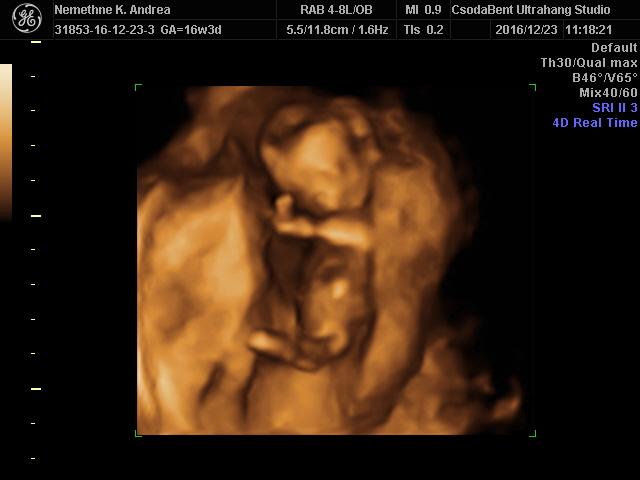

Mi pénteken megyünk a 4dre, és utána január végén lesz az 18.heti ultrahang, meg egy vér és vizelet.

De utána szép képeket és videót kaptunk róla, nagyon úgy néz ki hogy kisfiú!

Lilypie First Birthday tickers